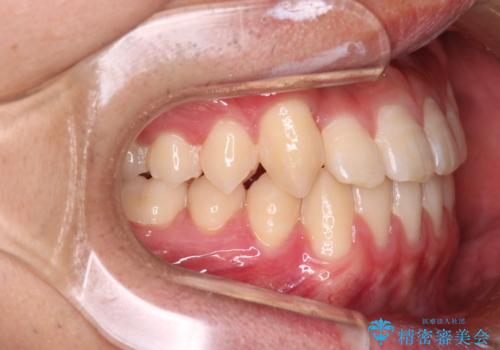

心配していた歯肉退縮も起こらず、前歯の噛み合わせと歯並びが綺麗に改善されました。

期間も1年2ヶ月と短期間で終了することができ、とても満足度の高い治療になりました。